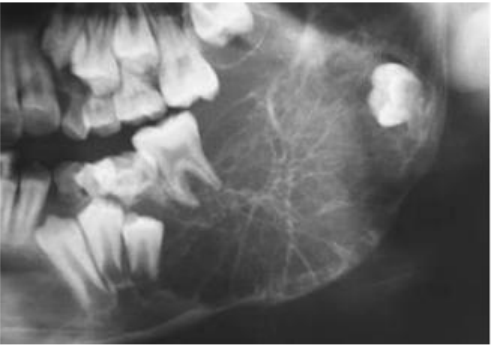

72. 下圖X光片中沿著左下顎齒槽神經管往前下走,在下顎骨體處可見一梭形膨大之放射線透過 性(radiolucent)影像,其臨床診斷最有可能為下列何者?

(A)Peripheral hemangioma (B)Central neurofibroma (C)Residual cyst (D)Central mucoepidermoid carcinoma